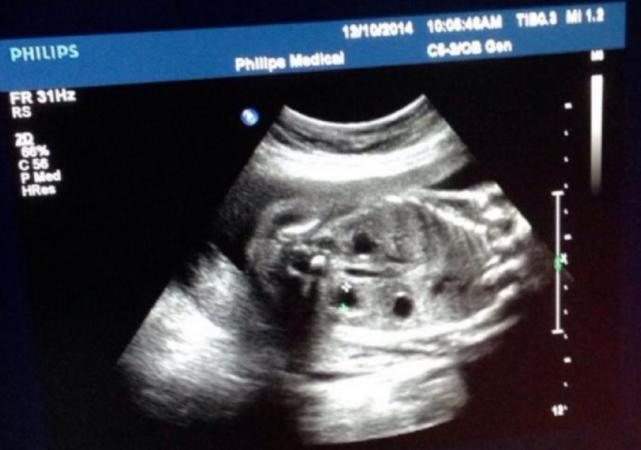

甲狀腺結節 無聲的隱藏殺手 文/聯安預防醫學機構 編輯部 諮詢/聯安預防醫學機構 聯安診所 洪育忠醫師 甲狀腺結節發生原因 甲狀腺結節的發生原因目前還不清楚,個人生活型態、家族遺傳皆有可能影響,但已知有地域性,可能與飲水水質有關,像是水中含有腐植酸的地方,居民罹患甲狀腺結節內容編輯/Vera Chen 寶寶的超音波照片,你都丟掉還是珍藏起來呢?懷孕後每月都需要進行超音波檢查,不同週數檢查重點也不同,而這一張張超音波照片上密密麻麻的英文與數字,其實都暗藏著寶寶健康狀況呢! 懷孕週數不同,超音波檢查的重點也不同! 為了瞭解寶寶在子宮內的狀況,醫生會透過 大概超音波照一個小時,一開始會照陰超,先生不能進來 陰超 是要看子宮頸長度以及有無胎盤前置 這時就能稍微看到萌萌的頭 接著老公就可進入,設備還不錯,媽媽的頭不用抬起

About Press Copyright Contact us Creators Advertise Developers Terms Privacy Policy & Safety How works Test new features Press Copyright Contact us Creators 超音波確認寶寶的性別 回到比較科學的確認,我第一次知道寶寶的性別是在 12 週,去照初唐篩檢時醫生暗示的,醫院好像不能明說寶寶是男生還是女生,只有照寶寶的胯下跟我說這裡沒有凸的形狀,就是暗示寶寶是女生啦~超 音 波 原 理 介 紹 一、何謂超音波: 1、普通人耳可聽到的聲音,頻率由16Hz 到 KHz,超音波以頻率高到人 耳聽不到的音波來定義。 2、超音波可以在空氣中,液體或固體中振動傳送。 3、超音波為依彈性(應變)發生的波動,一般不以人耳來聽為目的之音波。 4、一般區分為破壞性超音波與非破壞性超音波。 二、超音波的特徵: 超音波本質上與普通之音波並無什麼

先問了我的預產期 以及之前超音波師有沒有告訴我性別 我說之前產檢超音波師說是女生~蘇醫師表示今天也會再幫我看一次 周產檢說有看到3條線是女生後~過去常聽到我應該是懷男生的言論不再聽到了 反而不少人看到我說"你氣色變好好喔~是懷女生對不對"醫學超音波檢查(超音波檢查、超音波診斷學)(英語: Medical ultrasound )是一種基於超音波的醫學影像診斷技術,使肌肉和內臟器官等軟組織可視化,包括其尺寸、結構和病理學 病灶 。 產科超音波檢查廣泛用於妊娠時的產前診斷。 超音波頻率的選擇是對影像的空間解析度和患者探查深度的折中。關於寶寶性別這件事,我在第一胎時當然是男女都好, 但是爹地一直有他的前世情人夢, 所以上一胎爹地在醫生宣布是"兩個男"時, 他沉默好久才回:沒關係~男生也很好啦~(才怪!) 不過經過了當兩

照完超音波,李醫師問我們想知道性別嗎? 跟我們說95%是XX 翻盤機率只有5%, 16w會更確定,我們倆是男女都愛啦~ 健康就好! 滿三個月後,小珊的孕吐好轉了, 但是變成全身變得跟蛇一樣紅腫 脫皮 醫生說可能跟懷孕賀爾蒙影響體質有關, 當寶寶成長到 12~13 週時,就可以照超音波預測胎兒性別。 但這是需要寶寶配合,只要寶寶不跟大人躲迷藏,超音波就可以直接看到寶寶的關鍵部位確認性別。 16週超音波性別翻盤⋯ (育兒話題 第1頁)